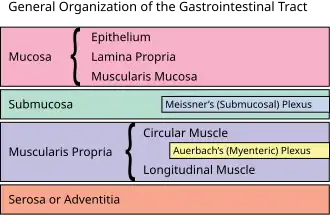

General structure of the gut wall showing the submucosa.

General structure of the gut wall showing the submucosa.